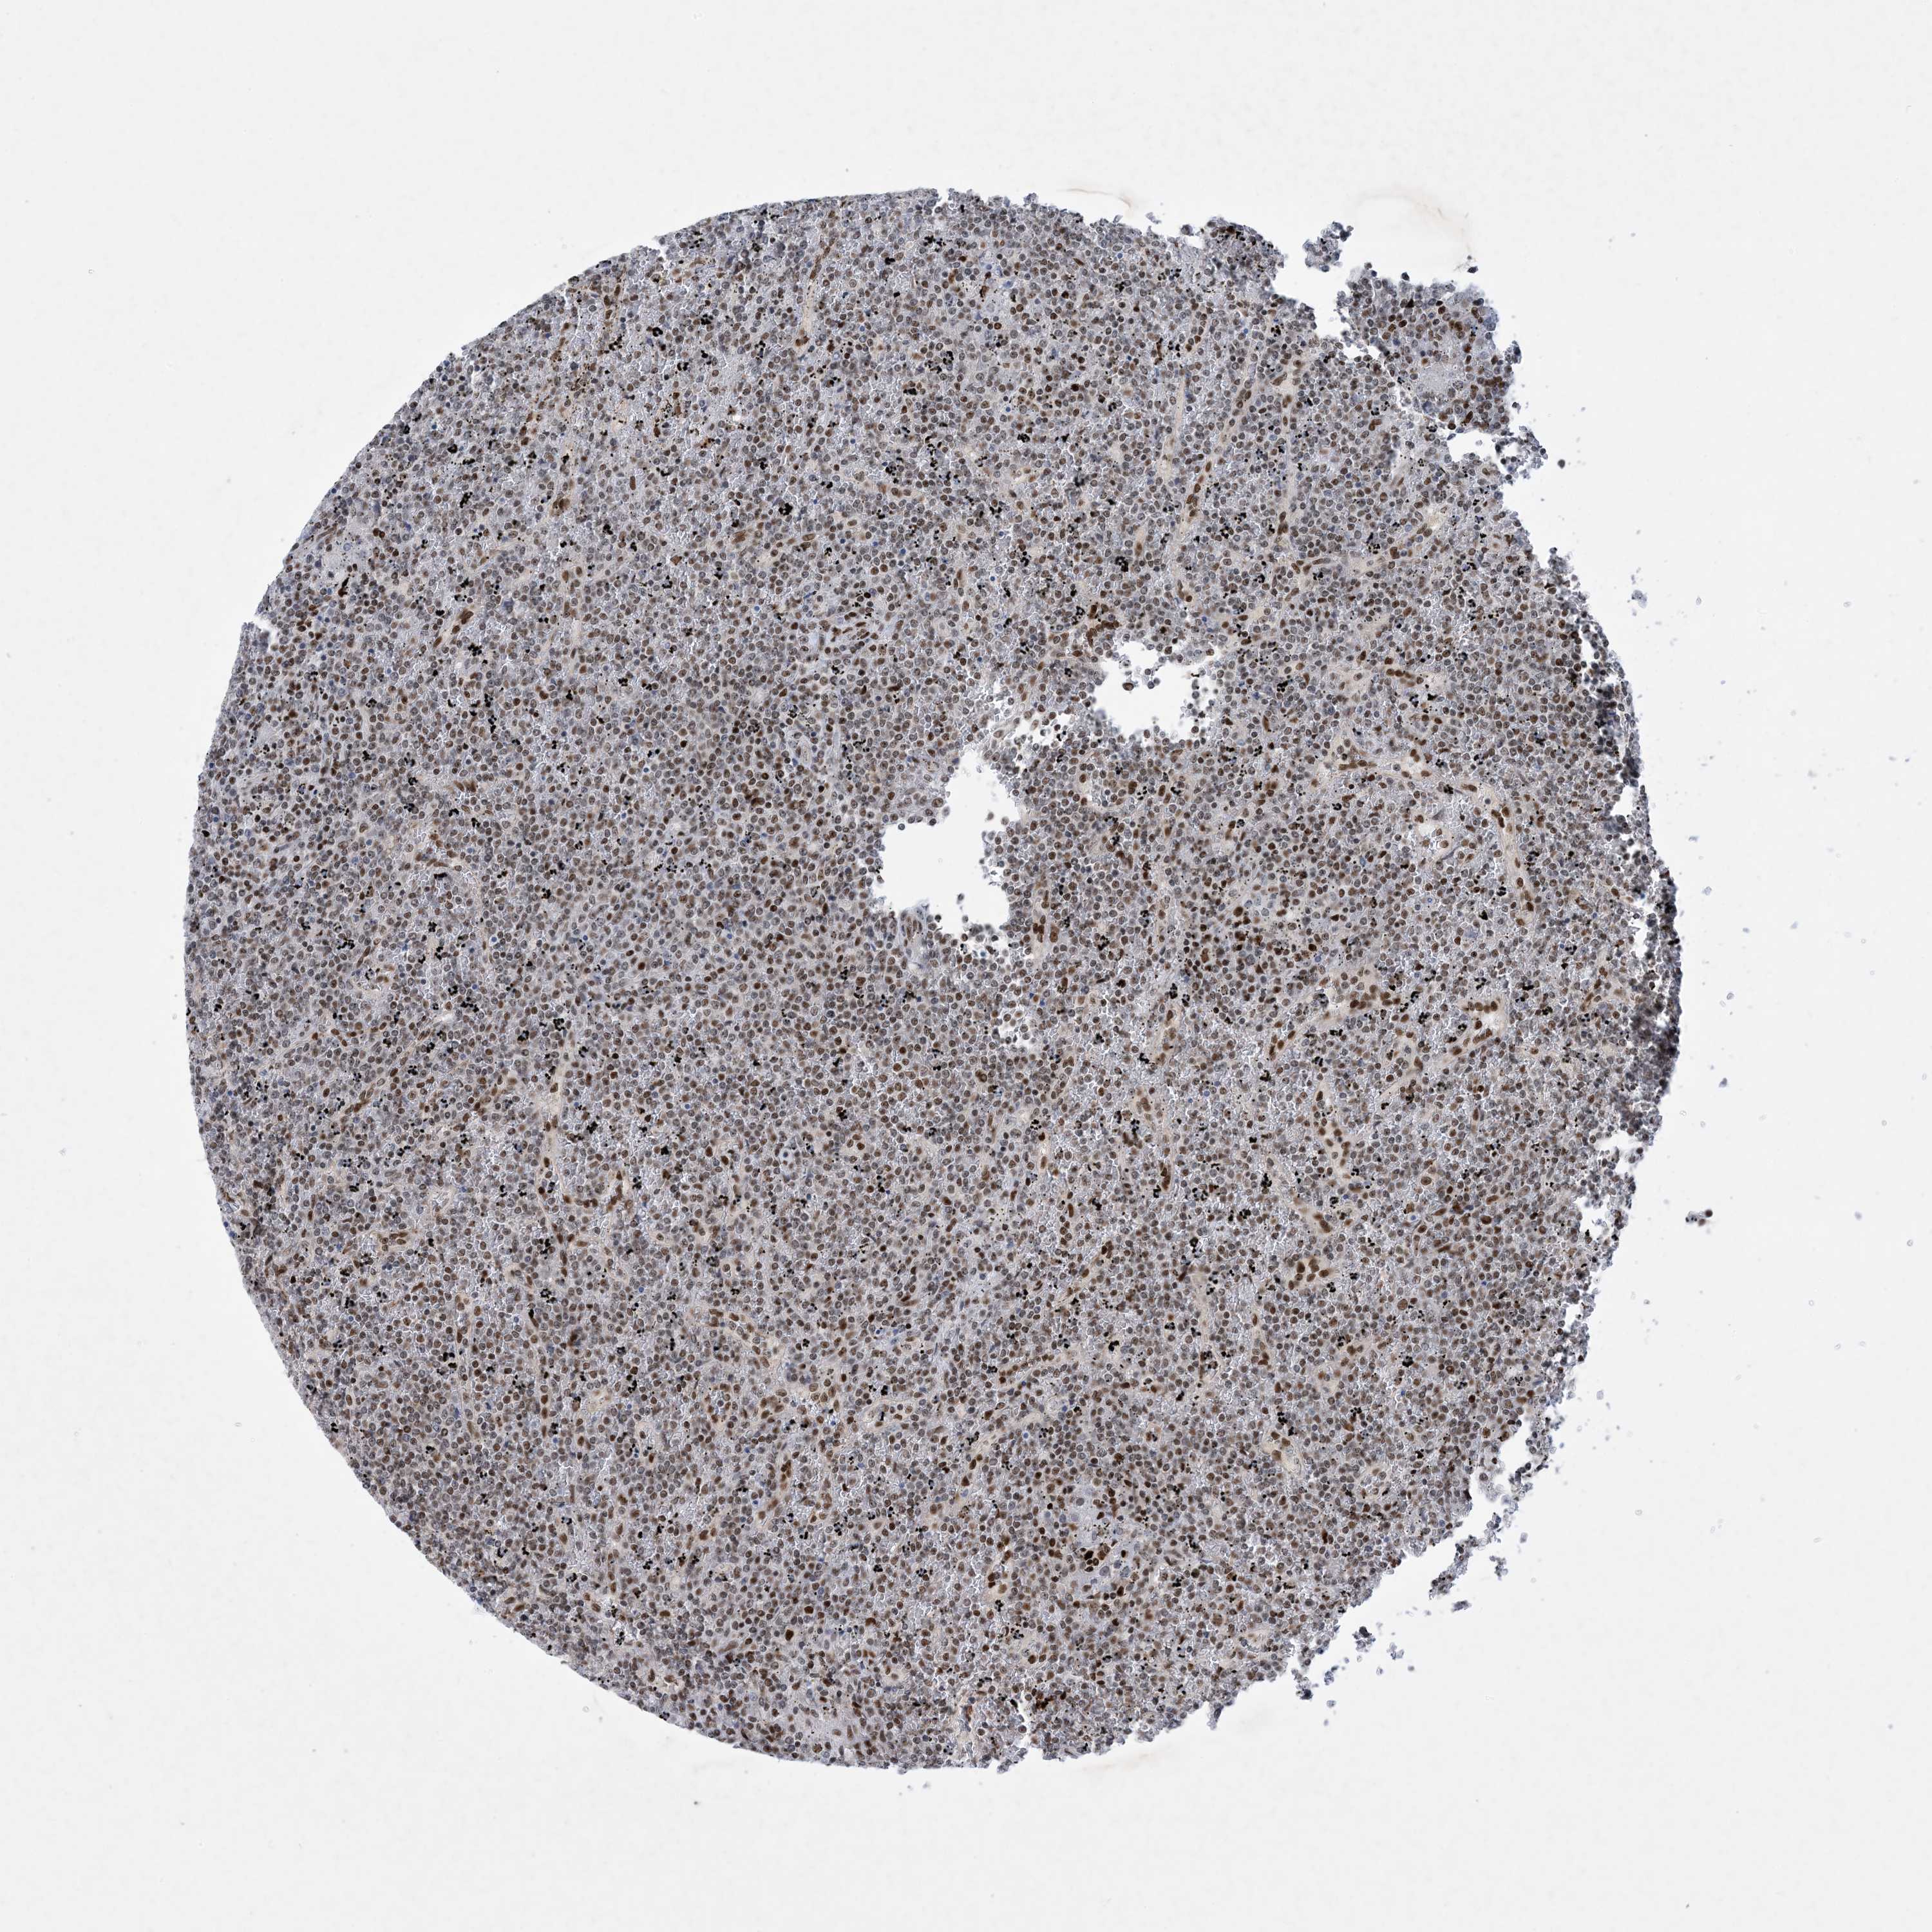

CANCER LYMPHOMA Show tissue menu

LYMPHOMA - Protein expressioni

A mouse-over function shows sample information and annotation data. Click on an image to view it in a full screen mode. Samples can be filtered based on level of antibody staining by selecting one or several of the following categories: high, medium, low and not detected. The assay and annotation is described here.

Antibody HPA031970

Staining

High

Intensity

Strong

Quantity

>75%

Location

Nuclear

Hodgkin's disease, NOS

Malignant lymphoma, non-Hodgkin's type, High grade

Malignant lymphoma, non-Hodgkin's type, Low grade